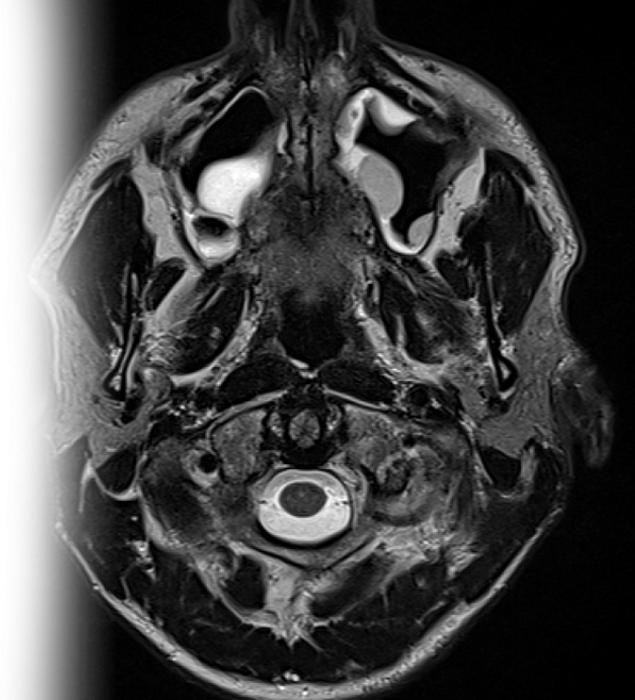

МРТ придаточных пазух носа

Магнитно-резонансная томография придаточных пазух носа – важный метод исследования, который позволяет оценить состояние придаточных пазух носа.